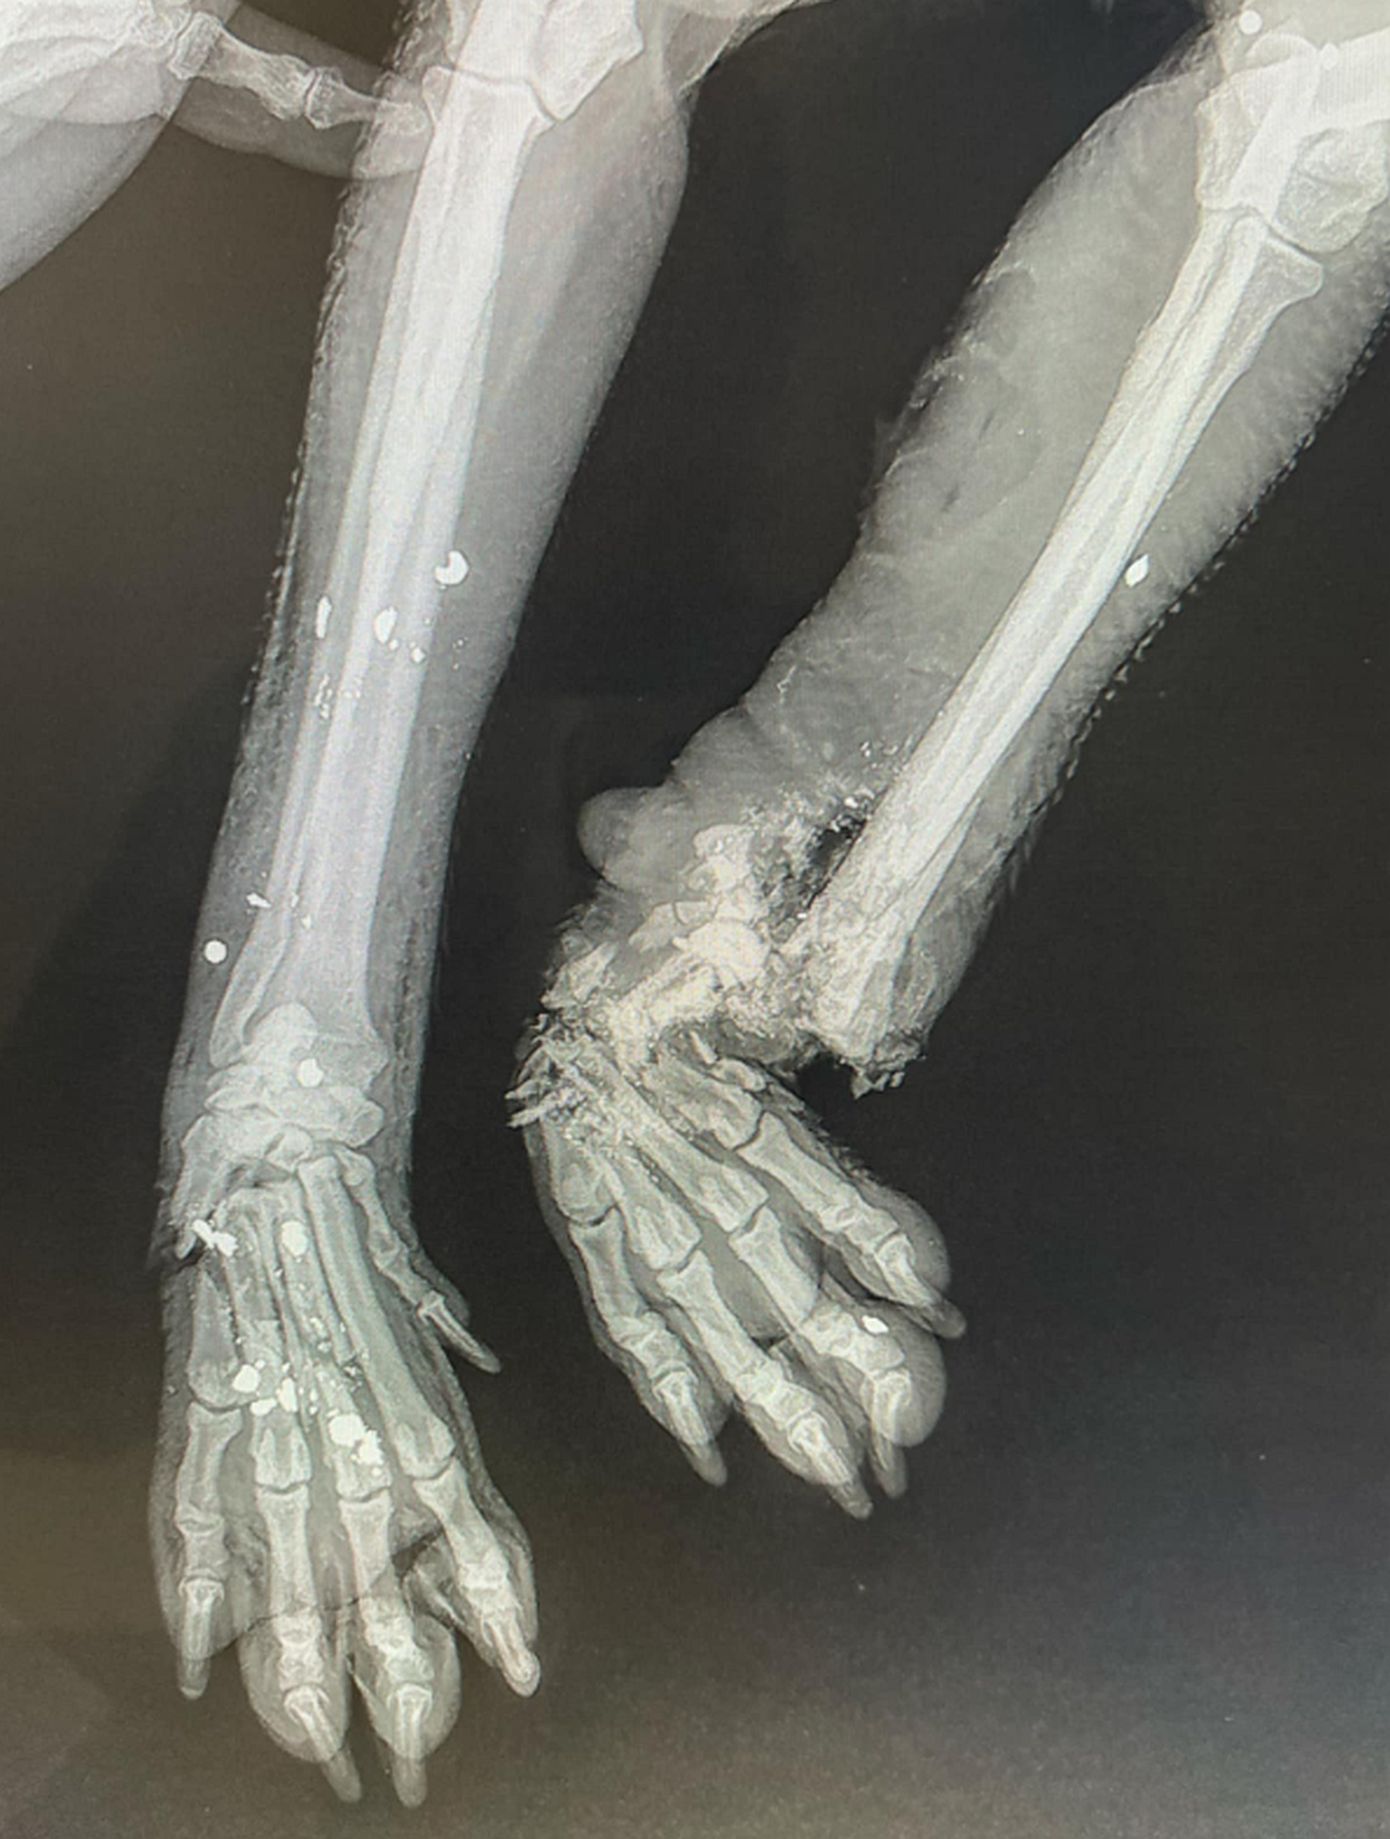

Η μικρόσωμη σκυλίτσα, η οποία από θαύμα είναι ακόμη ζωντανή, βρέθηκε σοβαρά χτυπημένη, με τα κόκκαλα στο ένα της πόδι να είναι κυριολεκτικά θρυμματισμένα, ενώ στο άλλο πόδι το κόκκαλο φαίνεται εκτεθειμένο. Παράλληλα, στο σώμα της βρέθηκαν και σκάγια, τα οποία επιβεβαιώνουν πυροβολισμό!

Ο δράστης της ακραίας κτηνωδίας παραμένει άγνωστος, τη στιγμή που η δίχρονη σκυλίτσα, με τρία πόδια πλέον, παλεύει να επανέλθει.